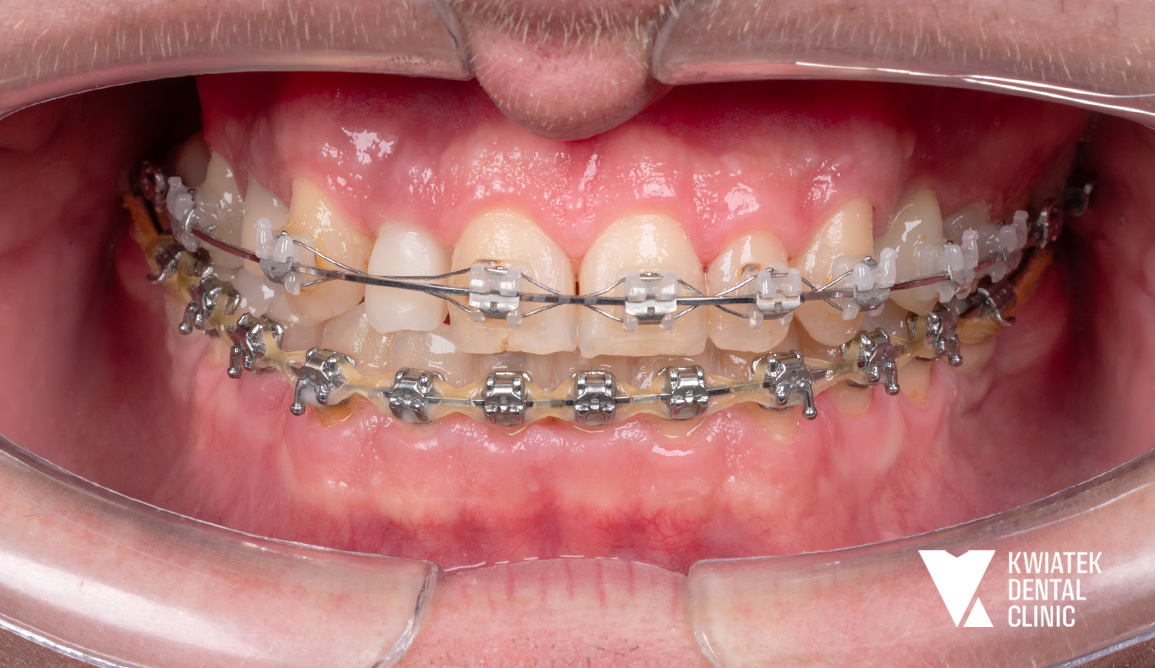

Po odbudowie fundamentów rozpoczęto leczenie ortodontyczne, którego celem była korekta ustawienia zębów i przygotowanie optymalnych warunków dla finalnej estetyki.